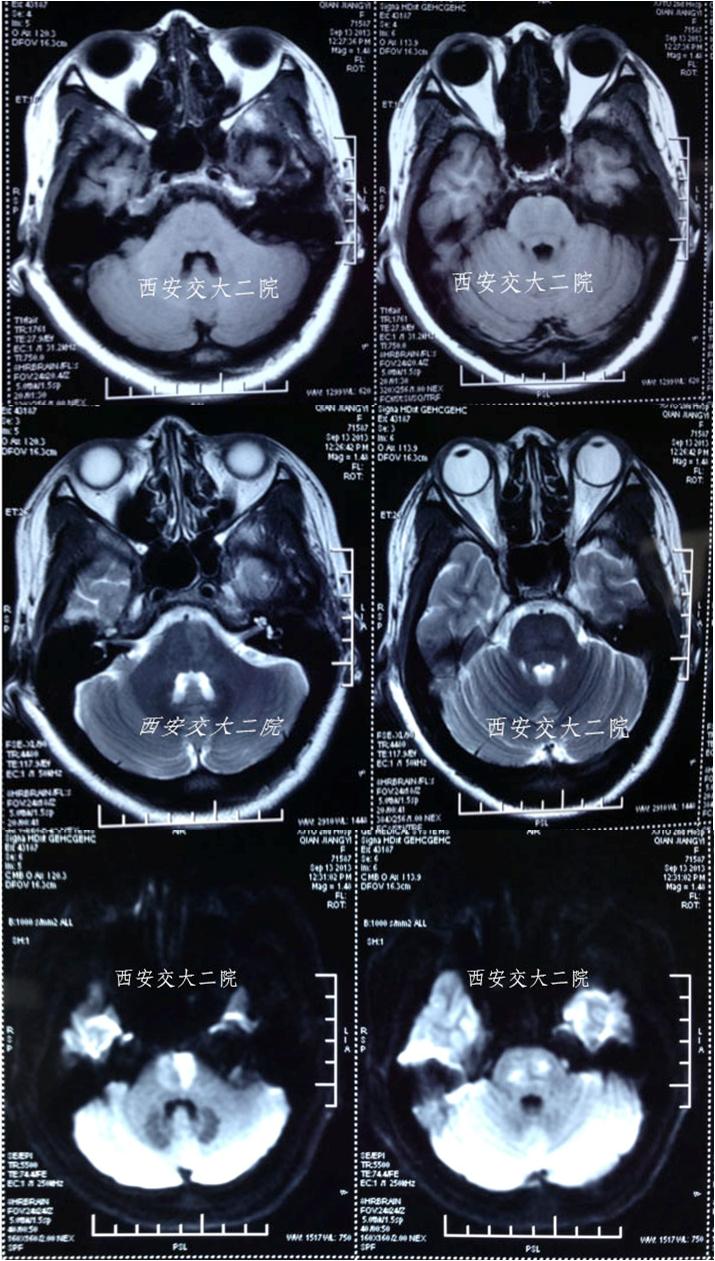

脑MR提示脑干大面积梗死

术前DSA